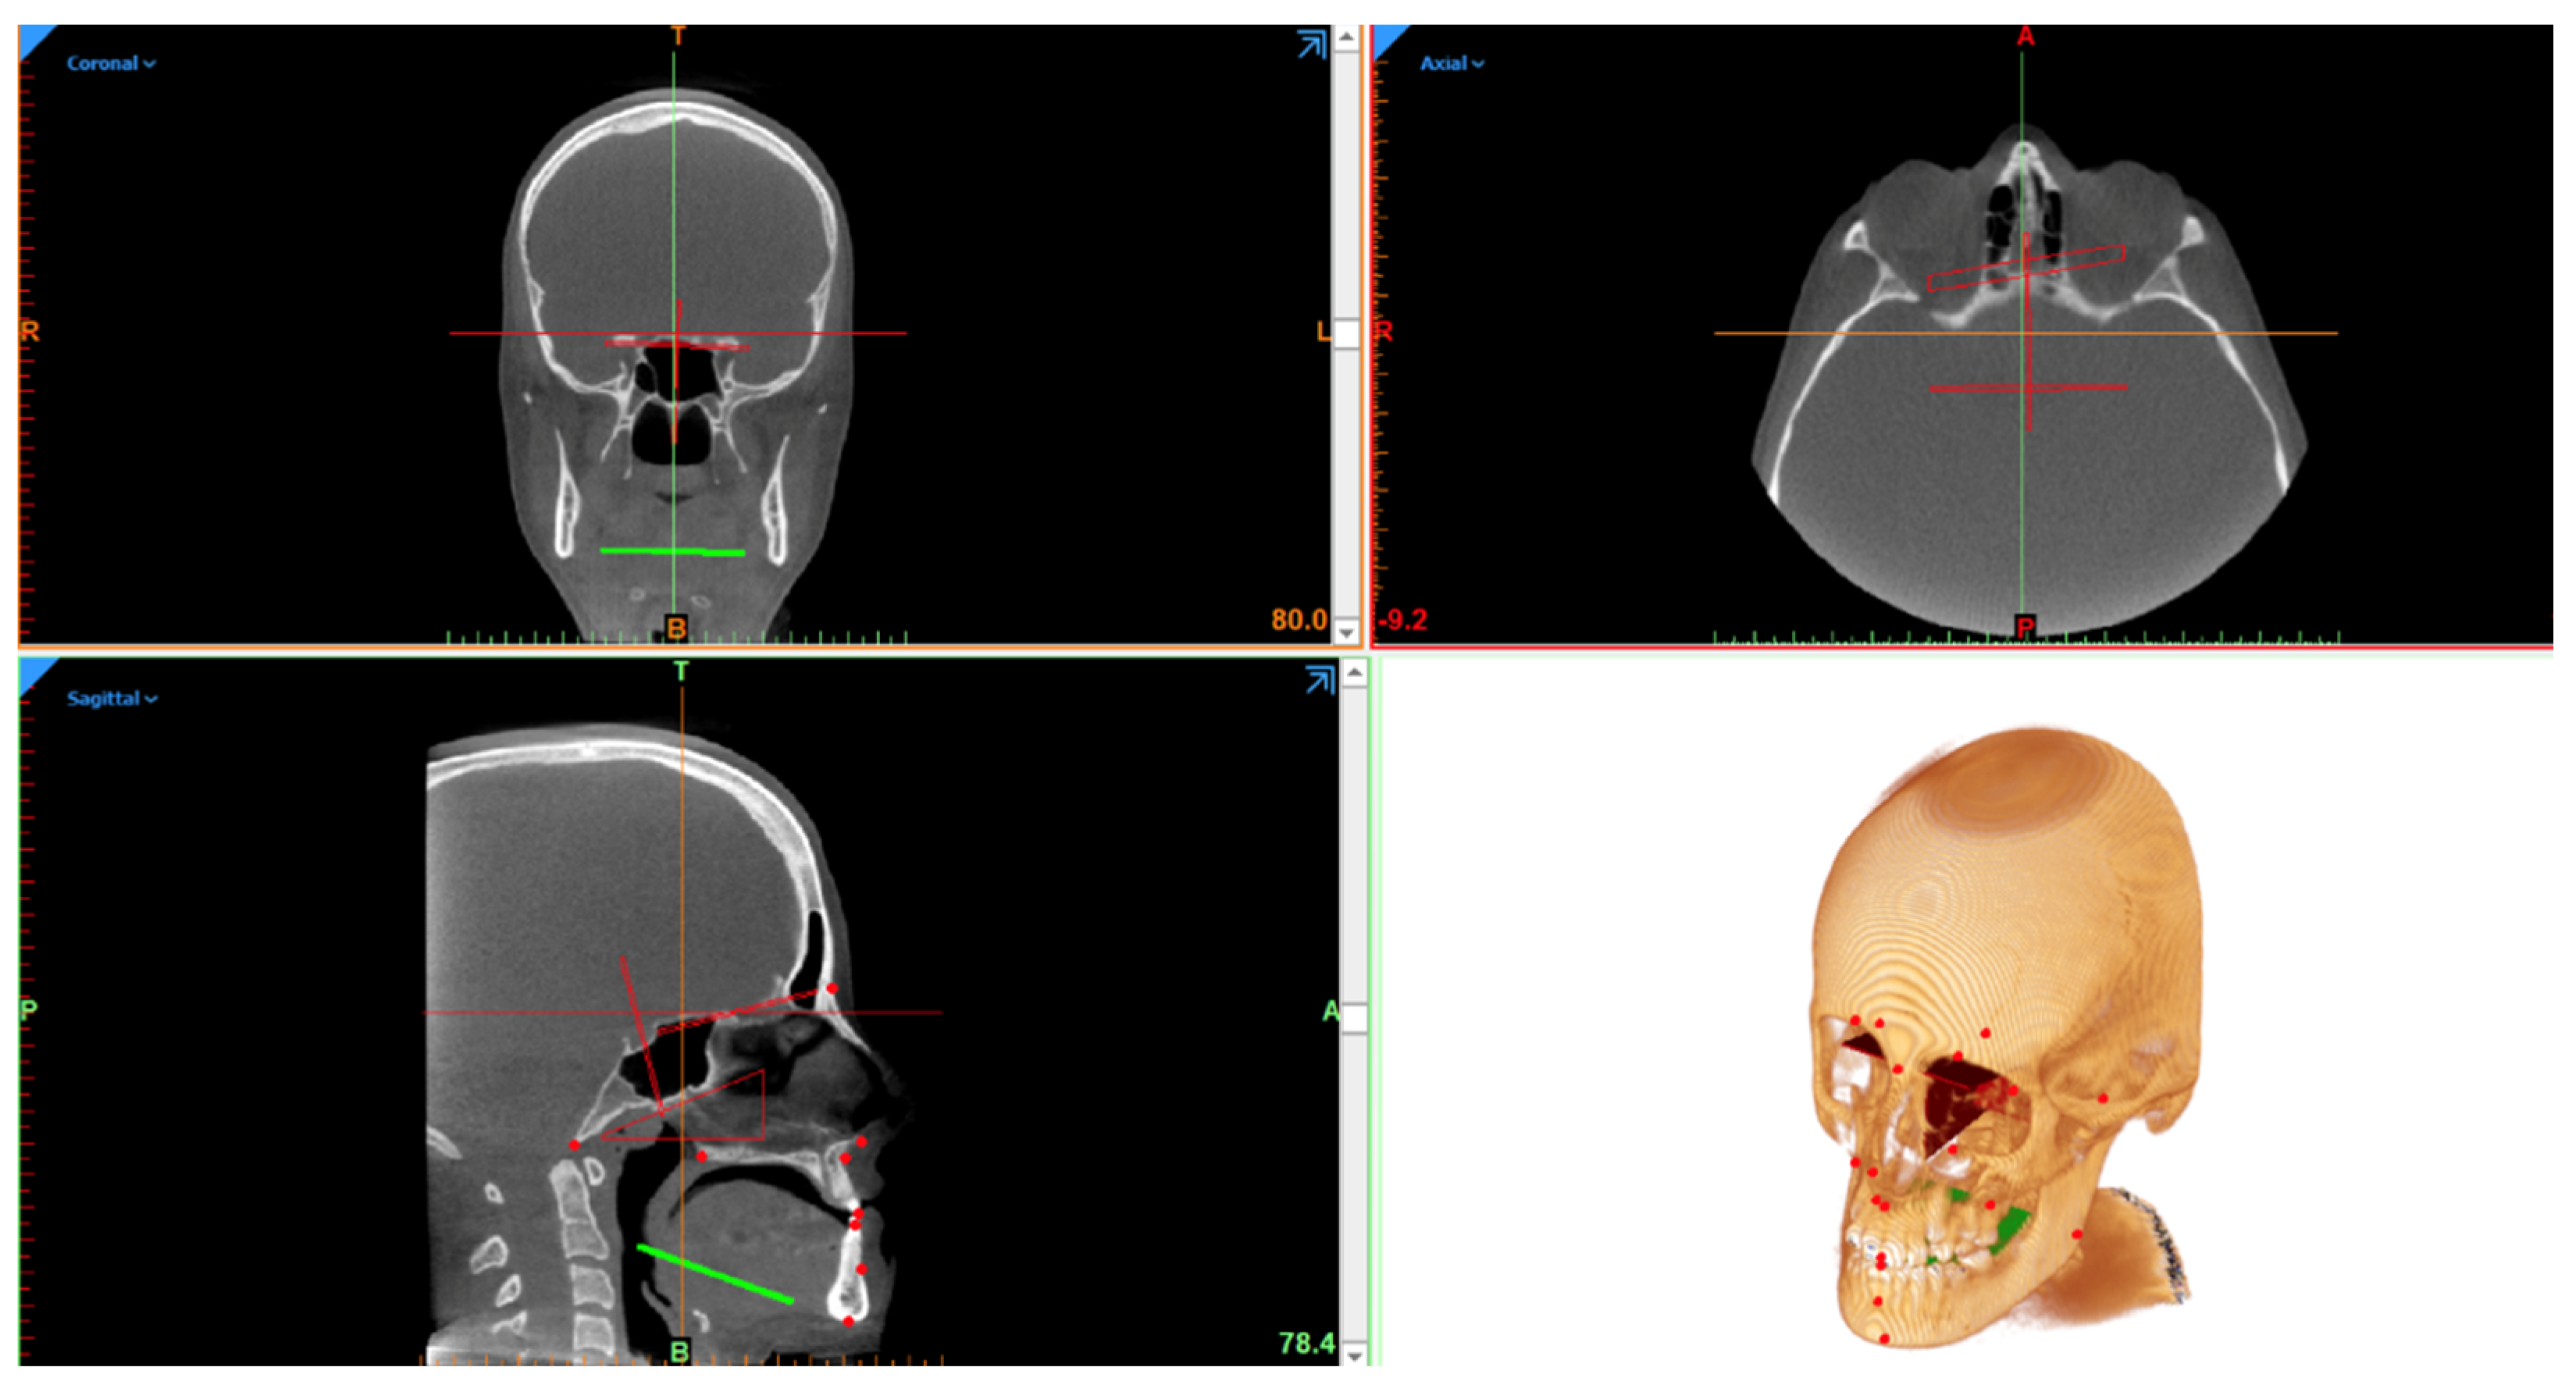

The ACM were performed accordingly and provided the betweenness centrality of the values of the go-sagittal plane (Figure 2). The closeness of the links in the following values can be evidenced with N-Me, Mx-Sagittal plane, Cd-Go-Me, S-N-Go-Me, and Cd-Go-N (Figure 3).

Figure 2.

Right go-sagittal plane betweenness centrality displayed on Pajek.

Figure 3.

Betweenness centrality displayed on Pajek, calculated with Auto Contractive Maps.